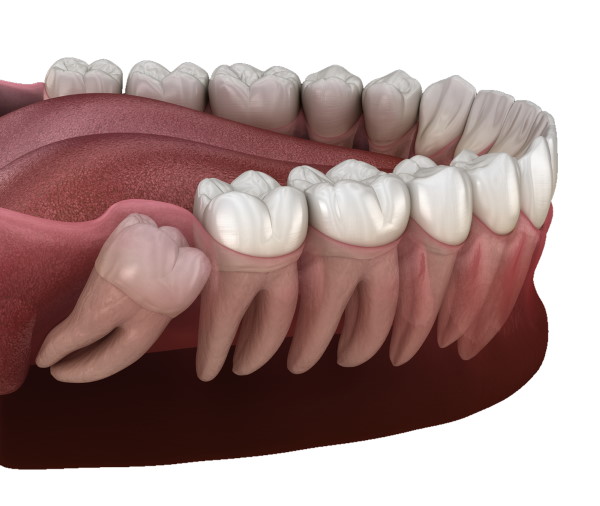

Wisdom tooth extraction and impacted wisdom teeth removal are common dental emergency services to remove impacted or infected wisdom teeth. Edge Dental provides safe wisdom tooth extractions in Houston, TX. If you would like to know more about wisdom teeth removal aftercare instructions that can make your recovery more comfortable. Please contact us today!